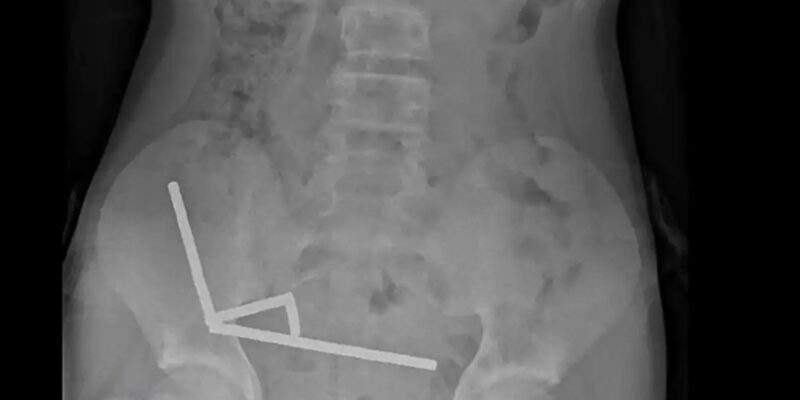

Μια σοκαριστική περίπτωση αντιμετώπισαν οι γιατροί στη Νέα Ζηλανδία, όταν ένας 13χρονος κατέληξε στο χειρουργείο αφού είχε καταπιεί δεκάδες ισχυρούς μαγνήτες, προκαλώντας σοβαρές βλάβες στο έντερό του. Κατάπιε περίπου 100 μαγνήτες και υπέφερε για μέρες Το περιστατικό καταγράφηκε στο νοσοκομείο Ταουράνγκα, στο βόρειο τμήμα της Νέας Ζηλανδίας, όπου το ανήλικο αγόρι διακομίστηκε ύστερα από τέσσερις […]Μετάβαση στην Πηγή ALLDAYNEWS